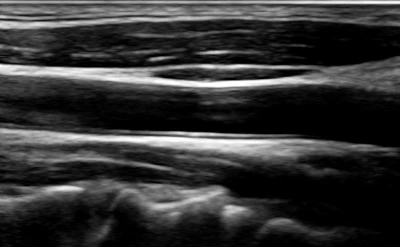

아래는 뇌혈류 초음파 (TCD, Transcranial Doppler)에 대한 검사 결과예요.

뇌혈류 초음파 (TCD, Transcranial Doppler)

검사 목적 : 뇌혈관의 혈류 속도, 방향, 혈관 협착(좁아짐) 여부 평가

tempImageE3NLlX.heic

tempImage5UoUr3.heic

뇌혈류 초음파 사진